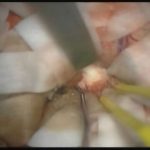

術中写真

摘出 前

摘出 中

摘出 後